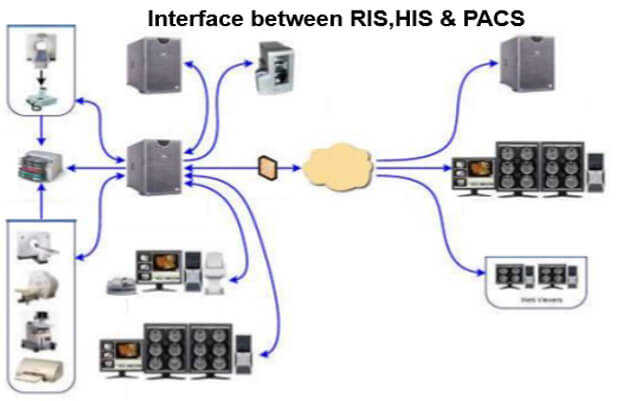

The work organization before the RIS- PACS integration:

Here we can see the work organization after the RIS-PACS integration. In fact, PACS is used by radiology personnel to manage the workflow of patient exams:

This simplified diagram indicates the image data flow between the imaging modality and PACS.

PACS is usually an integration of input from digital devices which may be any radiological modality. These devices include Image acquisition device, image storage server for short or long term storage of data, transmission network, display station, imaging work station, and user interface, camera to convert to hard copies images on a need basis, and integration to radiology information system and hospital information system.

This simplified diagram indicates the image data flow between the imaging modality and PACS.

- Flow: Modalities -> PACS

The flow of “raw” format images. Acquisition protocol for each modality (automation and technologist dependent).